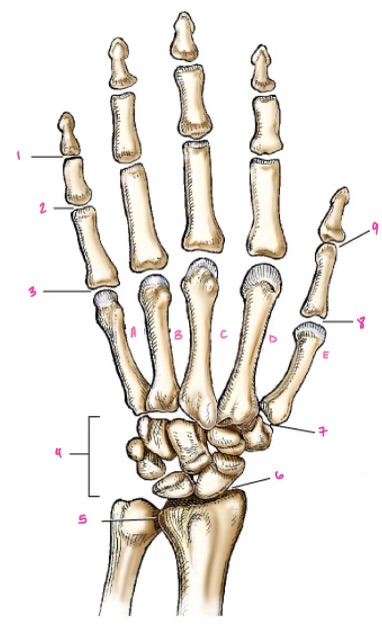

1

1

Hamate

2

2

Capitate

3

3

pisiform

4

9

Trapezoid

5

10

Trapezium

6

11

Scaphoid

7

14

Lunate

8

15

Triquetrum

9

16

Pisiform

10

17

Capitate

11

18

Hamate

1

Distal interphalangeal

13

2

Proximal Interphalangeal

14

3

Metacarpophalangeal

15

4

Intercapals

16

5

Distal radioulnar

17

6

Radiocarpal

18

7

Carpometacarpals

19

8

Metacarpophalangeal

20

9

Interphalangeal

7

Trapezoid

22

8

Trapzium

23

9

Capitate

24

10

Scaphoid

25

11

Lunate

26

13

Carpus

27

14

Triquetrul

28

15

Hamate

29

16

Metacarpus

30

17

Phalanxes